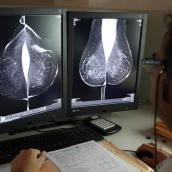

La Junta de Castilla y León defendió este jueves que gestiona con la “mayor celeridad posible” las segundas pruebas que se prescriben a las mujeres cuyas mamografías en los programas de cribado de cáncer de mama no descartan la existencia de lesiones